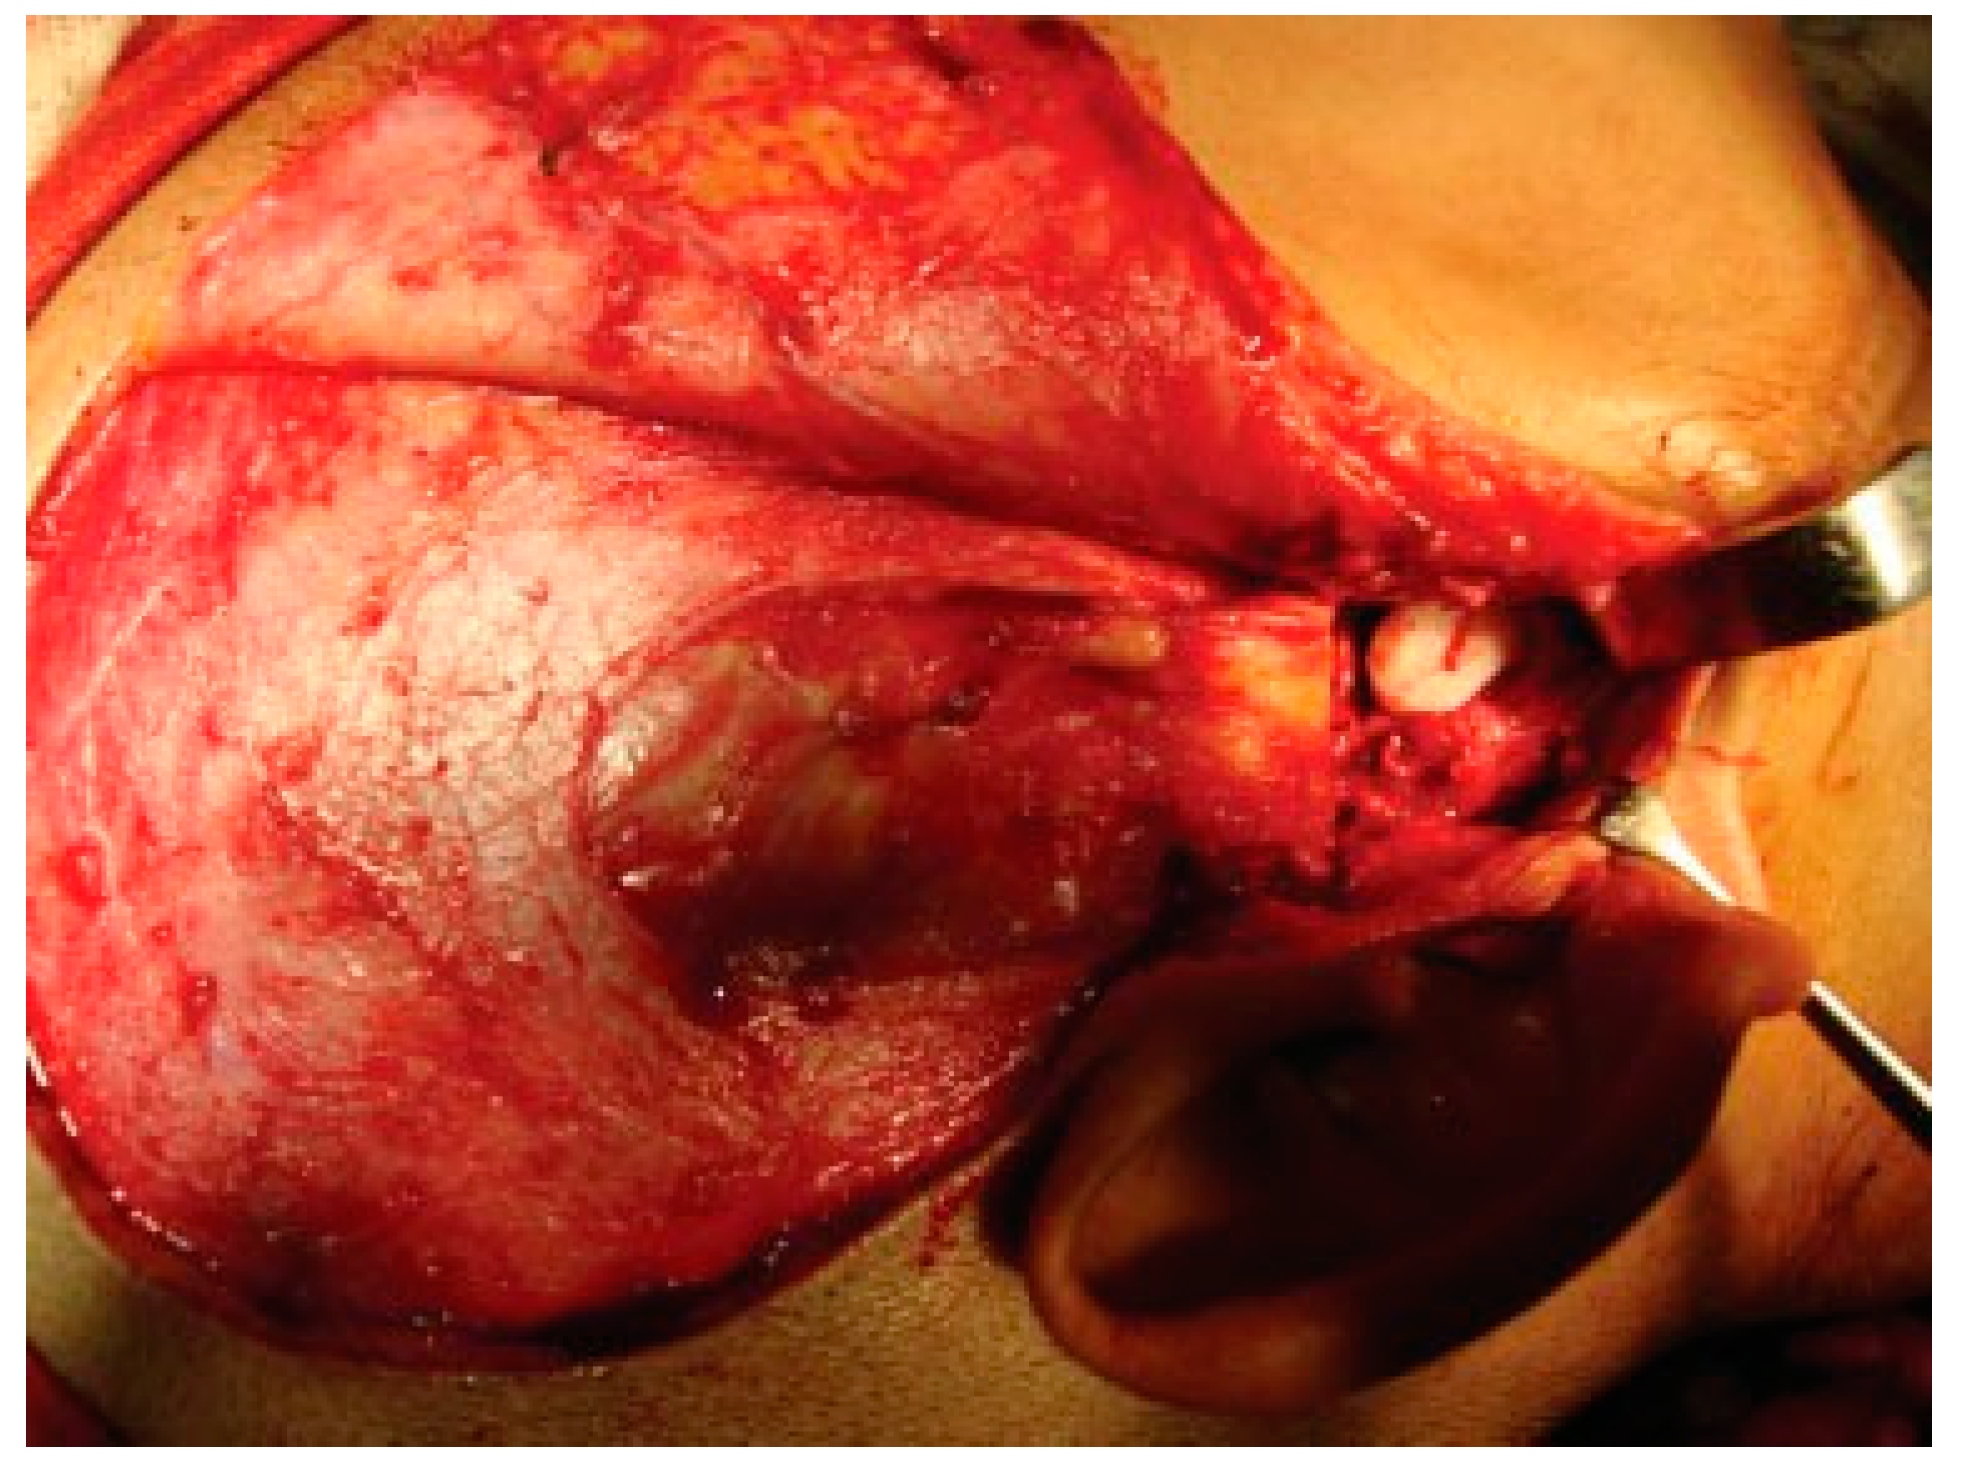

Reconstruction of the TMJ after release of ankylosis assumes paramount importance in terms of restoration of facial form and function. The goals of treatment in all the patients were the release of ankylotic mass, restoration of normal jaw form and function, symmetric growth of the mandible in children, and most importantly the prevention of reankylosis. All interpositional arthroplasties are to some extent the autogenous reconstruction of the morbid ankylotic TMJ after resection of the ankylotic mass. Merriam Webster Dictionary defines reconstruction as the act or process of building something that was damaged or destroyed again. Reconstructive surgery refers to a procedure whose goal is intended to restore form and function in structures deformed or damaged by disease, congenital anomaly, tumor, trauma, or infection (Farlex Partner Medical Dictionary Farlex 2012). The treatment of TMJ ankylosis is individualized based on the severity of ankylosis, age of the patient, and other patient factors. We have outlined our experience following Kaban’s protocol in the management of TMJ ankylosis. It is of paramount importance to obtain passive and maximal mouth opening using this protocol in terms of adequate resection and ipsilateral or contralateral coronoidectomy whenever required followed by aggressive physiotherapy (Figure 5 and Figure 6). Physiotherapy was started on third day postoperatively using Heister mouth gag five times a day during the hospital stay of the patient. This device was purchased by the patient after discharge from the hospital for physiotherapy at home. The MIMO and excursive movements were recorded at various follow-ups for all the patients. No intermaxillary fixation/elastics were applied to any of the patients in the series.

Figure 5. Intraoperative passive mouth opening.

Cmtr 09 i4f284 g005

Figure 6. Resected ankylotic chunk with coronoidectomy.

Cmtr 09 i4f284 g006